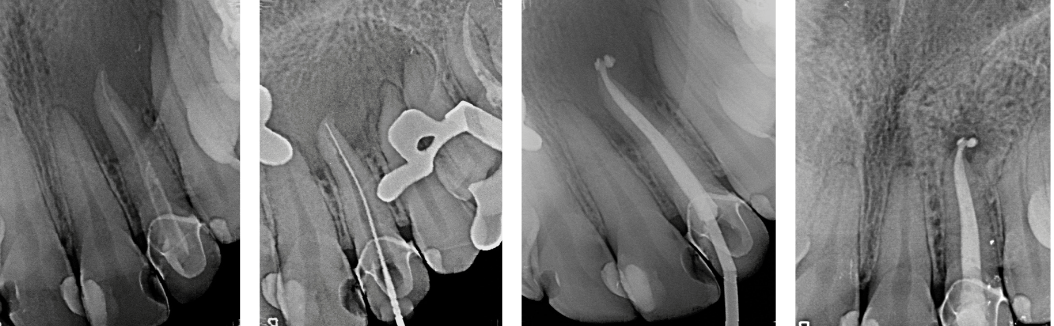

La cirugía endodóntica se puede usar para localizar fracturas o canales ocultos que no aparecen en las radiografías pero que aún manifiestan dolor en el diente. Las superficies radiculares dañadas o el hueso circundante también pueden tratarse con este procedimiento.

Se hace una incisión en el tejido de las encías para exponer el hueso y el tejido inflamado circundante. El tejido dañado se elimina junto con el extremo de la punta de la raíz. Se coloca un relleno en el extremo de la raíz para evitar la reinfección de la raíz y se sutura la encía.

El hueso se cura de forma natural alrededor de la raíz durante un período de meses restaurando su función por completo.